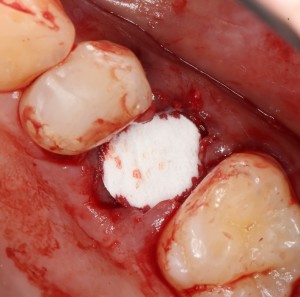

Биоматериал не нужно предварительно смачивать или увлажнять, он просто помещается в лунку в нужное положение:

Обратите внимание — у лунки отсутствует часть вестибулярной стенки. При использовании порошкообразного или гранулированного материала, мне пришлось бы отграничивать эту вестибулярную стенку с помощью барьерной мембраны. При использовании BioOss Collagen чаще всего этого не требуется.

Сам же материал достаточно гигроскопичен, чтобы быстро пропитаться кровью из лунки. Напомню, что именно жидкости являются транспортной средой в нашем организме, поэтому гидрофильные свойства во многом определяют способность биоматериала к интеграции:

Нет необходимости заполнять биоматериалом всю лунку. Не нужно заталкивать его в периапикальные области. Не забывайте о задаче — в первую очередь, нас интересует положение вестибулярной стенки, именно ее мы должны удержать на месте. Поэтому позиционируем наш графт, в основном, в верхней трети лунки: